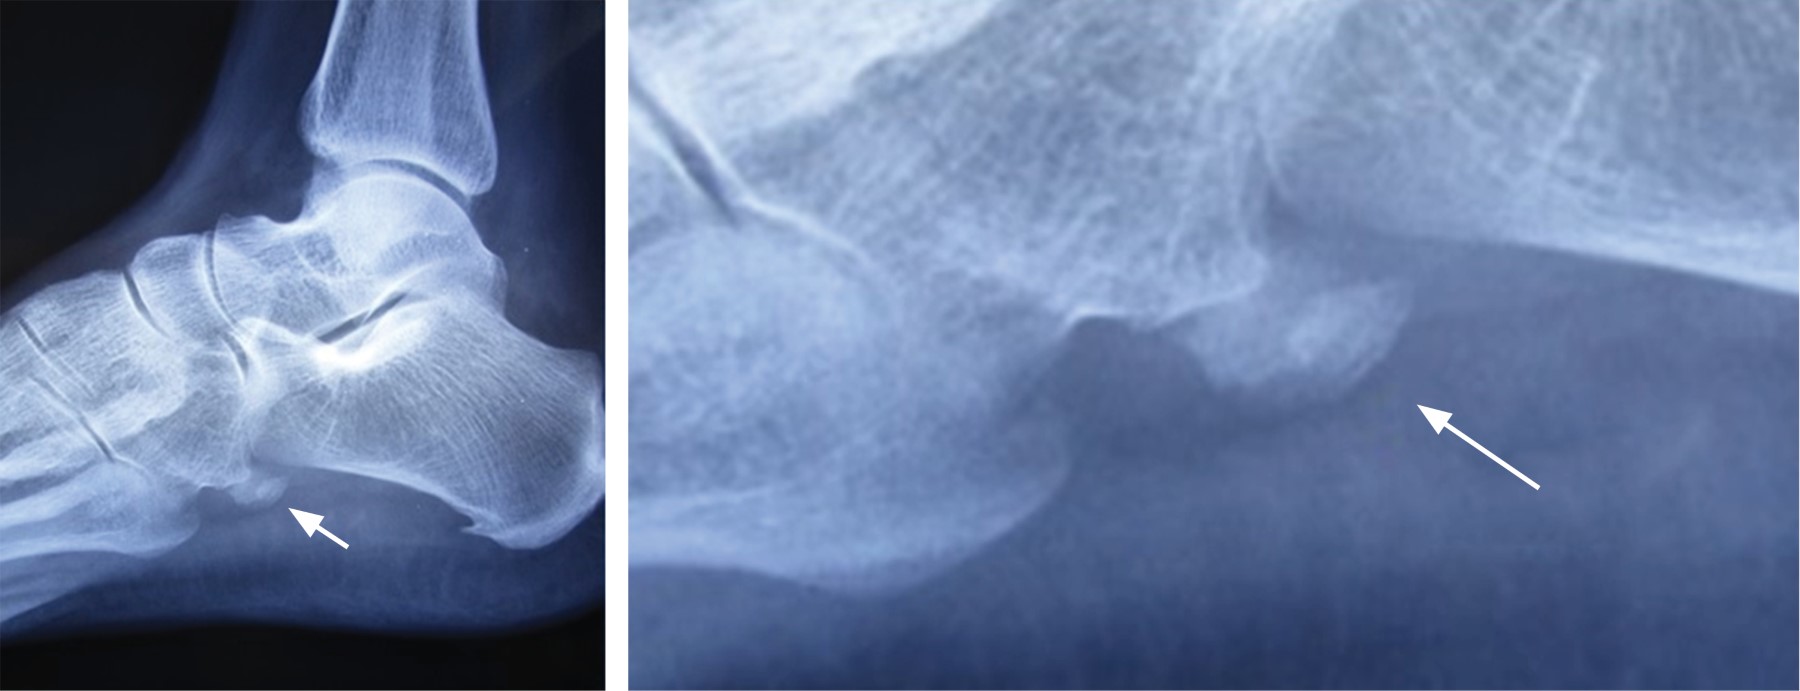

Paciente femenino de 40 años, maestra de primaria, sin antecedentes de importancia, quien acude por dolor de 10 días de evolución en cara lateral de medio pie izquierdo, el cual se presentó posterior a "saltar la cuerda durante el recreo con sus alumnos", a la exploración física dirigida, marcha claudicante a expensas de pie izquierdo, por dolor en cara lateral sobre cuboides, que se exacerba al pararse de puntas, edema moderado a 1 cm posterior a apófisis estiloides del quinto metatarsiano, dolor exquisito a la presión del cuboides y apófisis estiloides del quinto metatarsiano, con movimientos completos de pie y tobillo muestra dolor, con movilización activa en eversión, pulsos y llenado capilar normales. Con diagnóstico presuncional de avulsión del peroneo corto se solicitaron radiografías de pie izquierdo que revelaron: presencia de Os peroneum con calcificación difusa con discontinuidad cortical, fragmentación, márgenes irregulares, densidad heterogénea y edema (Figura 1). Se decidió tratamiento conservador con meloxicam 15 mg/día por 10 días e inmovilización por cuatro semanas y descarga con muletas axilares, seguida de tres semanas de rehabilitación con apoyo paulatino, dándose de alta asintomática.

Figura 1